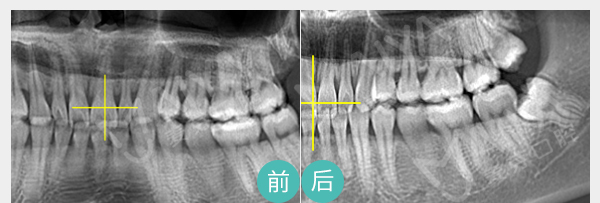

• 麦芽龈下洁治

针对牙周炎、不良修复体导致的牙周袋, 麦芽龈下刮治术通过精密器械,清除根面结石和菌斑创口小愈合快,但建议根治牙周炎或更换不良修复体,才能治本

适应症:牙龈炎、牙周炎、 牙周袋、不良修复体引起的口臭